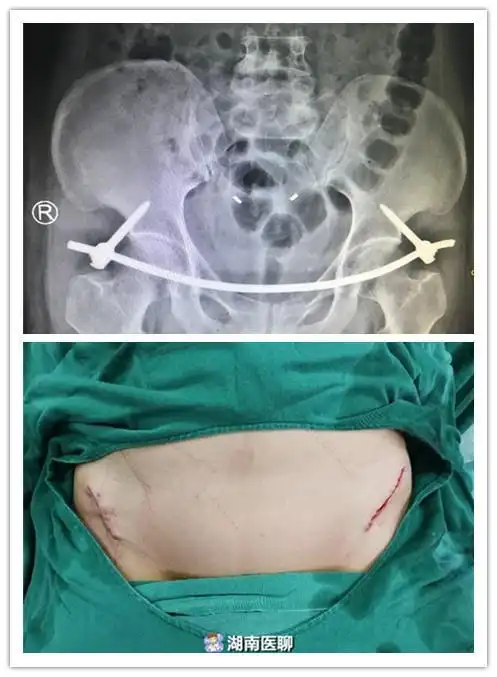

55岁女子车祸骨盆骨折手术后像没事人仅腰上两个小口子